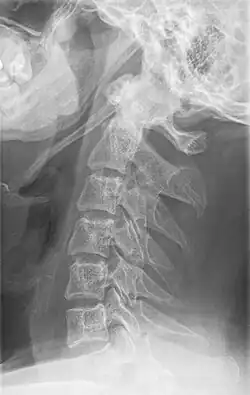

Radiograph, lateral view showing elongated stylohyoid process and stylohyoid ligament ossification -

Diagnosis is suspected when a patient presents with the symptoms of the classic form of "Eagle syndrome" e.g. unilateral neck pain, sore throat or tinnitus. Sometimes the tip of the styloid process is palpable in the back of the throat. The diagnosis of the vascular type is more difficult and requires an expert opinion. One should have a high level of suspicion when neurological symptoms occur upon head rotation. Symptoms tend to be worsened on bimanual palpation of the styloid through the tonsillar bed. They may be relieved by infiltration of lidocaine into the tonsillar bed. Because of the proximity of several large vascular structures in this area this procedure should not be considered to be risk free.

Imaging is important and is diagnostic. Visualizing the styloid process on a CT scan with 3D reconstruction is the suggested imaging technique.[13] The enlarged styloid may be visible on an orthopantogram or a lateral soft tissue X ray of the neck.